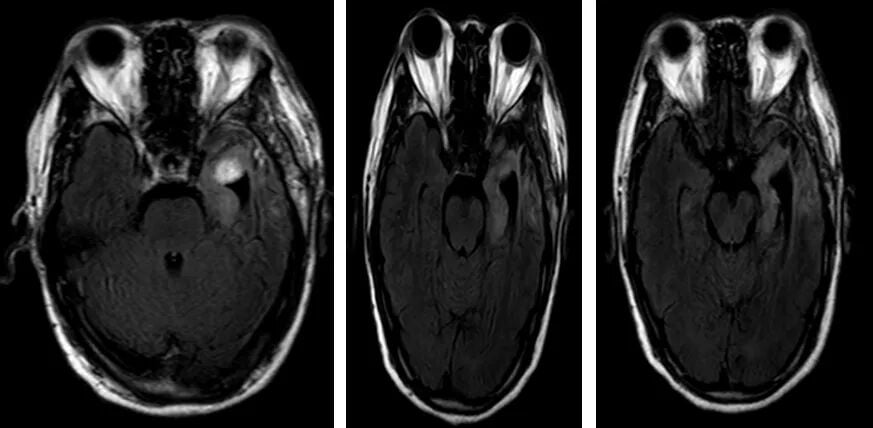

然而,好景不长。2022年1月,复查MRI提示疾病进展。医生调整方案,采用替莫唑胺联合贝伐珠单抗进行二线治疗。该方案在初期取得了良好效果,影像学评估为部分缓解(PR)并维持稳定。但后续因故治疗中断,至2023年3月,MRI再次确认肿瘤复发。

图3. 替莫唑胺联合贝伐珠单抗治疗期间的影像学变化